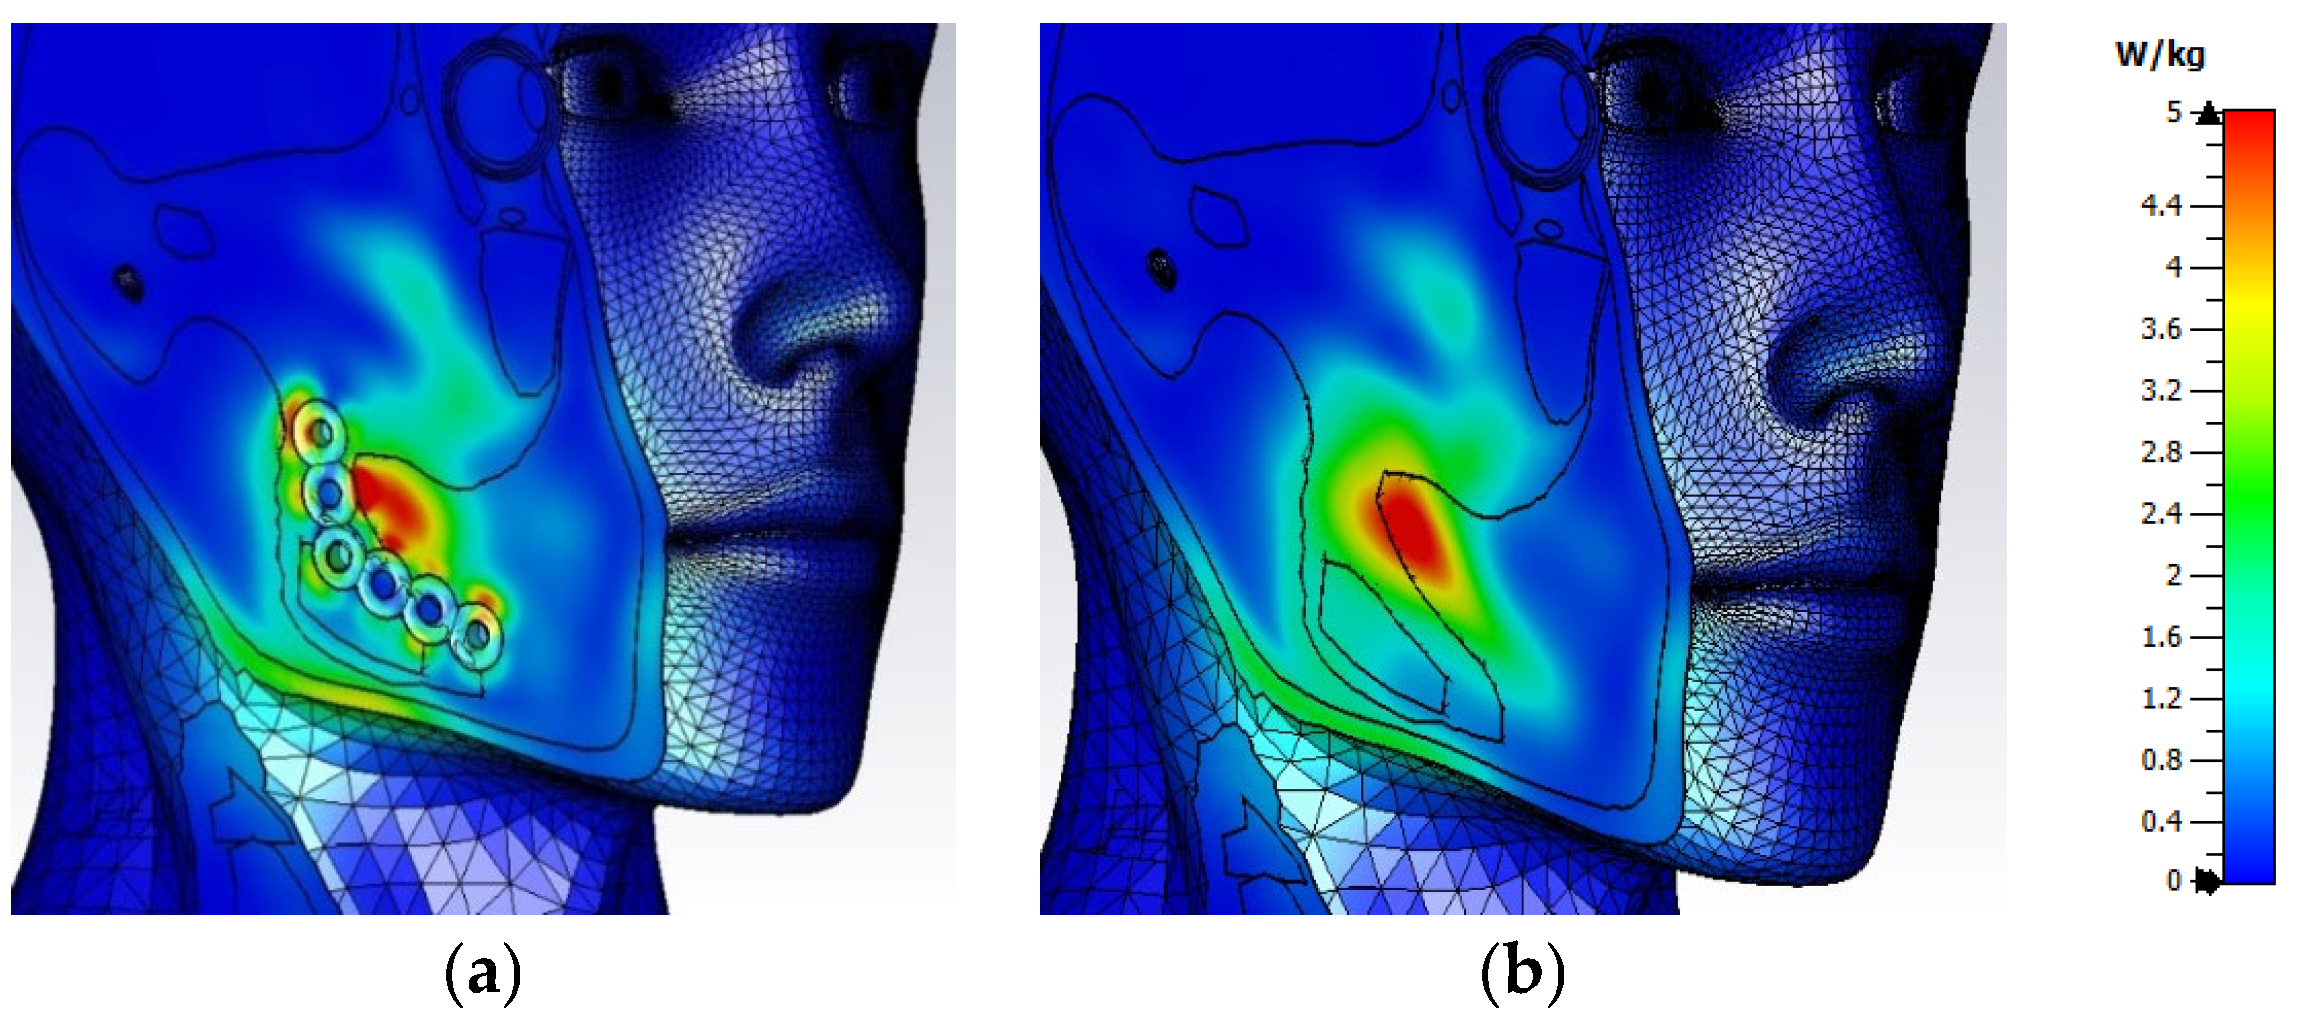

3.1. Electric Field Distribution Inside the User’s Head

3.2. Distribution of SAR Values Within the Model of the Head of a User